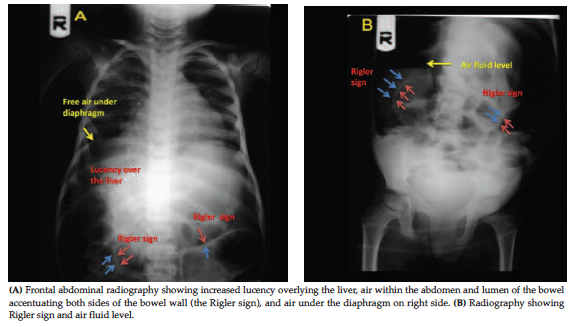

Abdominal radiography showed increased lucency overlying the liver, the Rigler sign, air fluid levels within the bowel loops, and air under the diaphragm (Figure 1A and 1B). She underwent an operation and received broad-spectrum antibiotics. Intraoperative findings revealed multiple small bowel perforations and peritonitis; therefore, a small bowel resection was done. During follow-up, the patient died due to sepsis. It should be noted that written informed consent was taken from her parents before study.

Air under the diaphragm on the right side of the abdomen is the most frequent sign of pneumo­peritoneum; the second most common sign is Rigler sign, characterized by the presence of air in luminal and peritoneal sides of the bowel loop.1,2 Therefore, physicians must be familiar with Rigler sign, as illustrated in Figure 1, because accurate and early diagnosis of intestinal perforation by clinical symptom, presence of Rigler sign in abdominal radiography, and then early surgical treatment can reduce mortality. It is also recommended that, in PTLD patients with gastrointestinal involvement who are scheduled to take rituximab, the surgeon should be informed to be ready for complications.